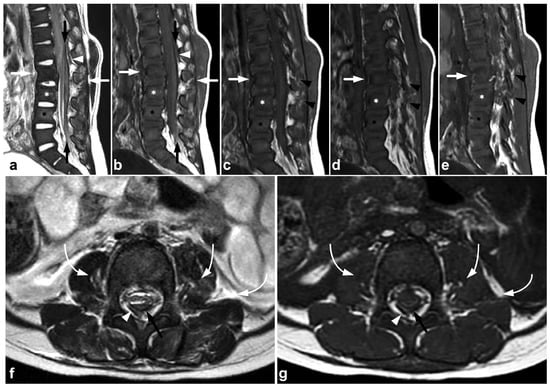

Figure 1.

(a) Sagittal T2-weighted. (b) Sagittal T1-weighted. (c) Sagittal STIR. A 9-year-old female, emergency MRI after a horseback riding accident. MRI demonstrates traumatic changes in vertebral bodies Th3–Th9, of which Th5, Th7, and Th8 have structural compressions (arrows). Th3, Th4, Th6, and Th9 have contusions without visible height loss (arrowheads).

Figure 2.

(a) Sagittal T2-weighted. (b) Sagittal T1-weighted. (c) Sagittal STIR. (d) Axial T2-weighted. A 16-year-old female, back pain after falling down the stairs. Burst fracture in L2 (arrow) with a fragment protruding into the spinal canal and compressing the conus medullaris. Edema can be seen in the conus medullaris immediately above the most compressed level (small arrow). In L4, there is a stable compression fracture (arrowheads). No intraspinal hematoma can be seen. Minor paraspinal edema/hematoma is best demonstrated in the axial image (d).